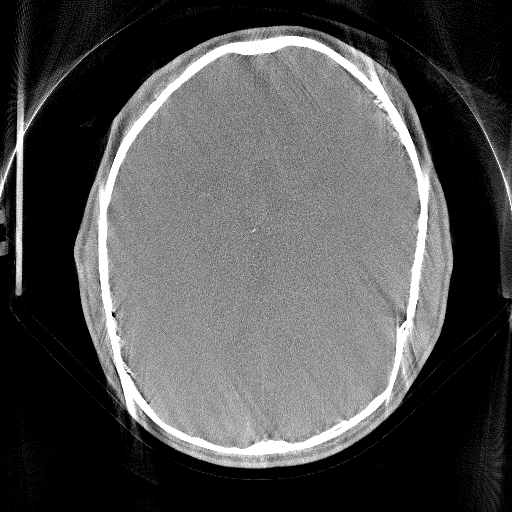

We use Adam optimization with learning rate of 0.000010.000010.00001 and select the network parameters that achieved the best RPE prediction on our validation dataset. Our network achieves an average RPE deviation from the Gt of 0.0310.0310.031 mm on the test dataset, as depicted in Fig. 1.

Figure 1: Network estimated RPE and different reconstructions, all revealing a RPE of 0.34absent0.34\approx 0.34 mm.